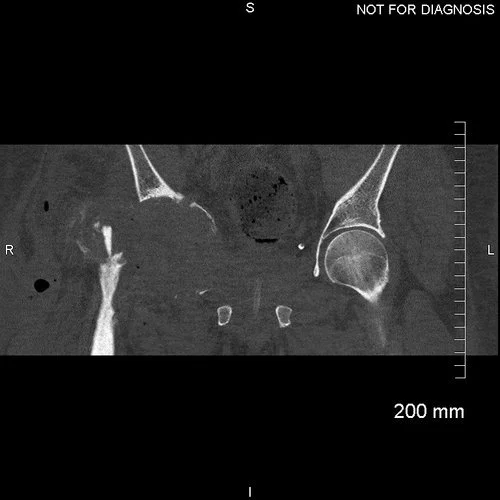

Anteroposterior and lateral plain radiographs showing a good position of the custom acetabular component and a well-cemented femoral stem.

EOS scanning at six-months after the second operation showed good positioning in the functional positions of sitting (with no stem-cup impingement) and standing (with equal leg lengths).

Coronal CT demonstrating an adequately seated implant with sufficient screws fixed to acetabular bone.